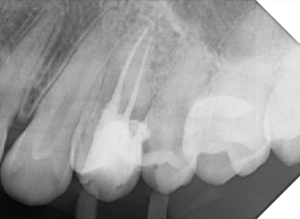

Alguns trabalhos